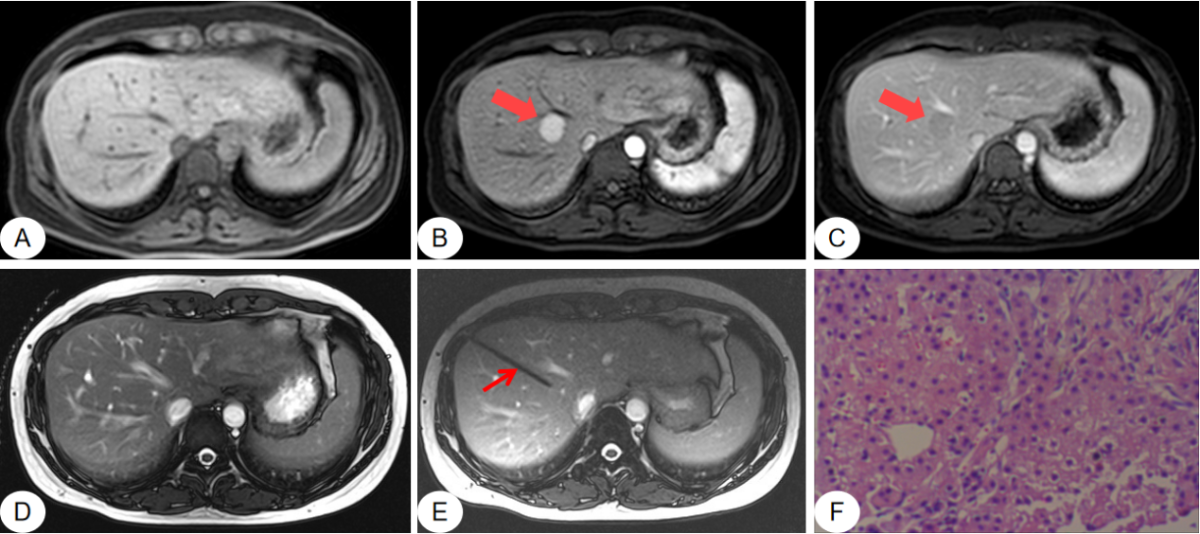

(2)磁共振引导下肝穿刺活检

磁共振T1WI(图A)、T2WI(图D)肝内未见明显病变,增强扫描动脉期(图B)病灶明显强化(红色粗箭),延迟期(图C)造影剂洗脱(红色粗箭);在磁共振引导下行穿刺活检(图E),穿刺针显示为低信号(红色细箭),无伪影;(图F)病理报告:穿刺组织倾向肝腺瘤。